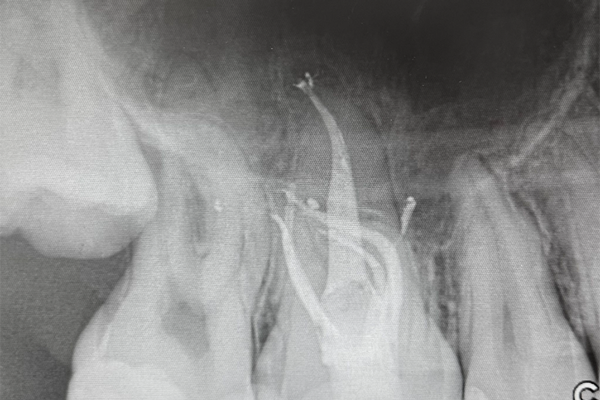

- Navigate Curved and Severely Calcified Canals

- Develop skills in handling curved root canals, minimizing risks such as canal transportation and perforation.

- Learn strategies for negotiating and treating severely calcified canals using the latest tools and techniques to restore optimal canal anatomy.

- Expertly Treat MB2 Canals in Maxillary Molars

- Master the techniques for locating and treating the often-missed MB2 canal in maxillary molars, improving treatment success in these complex cases.

- Learn the diagnostic and operational steps to identify MB2 canals, including using advanced imaging and magnification tools.